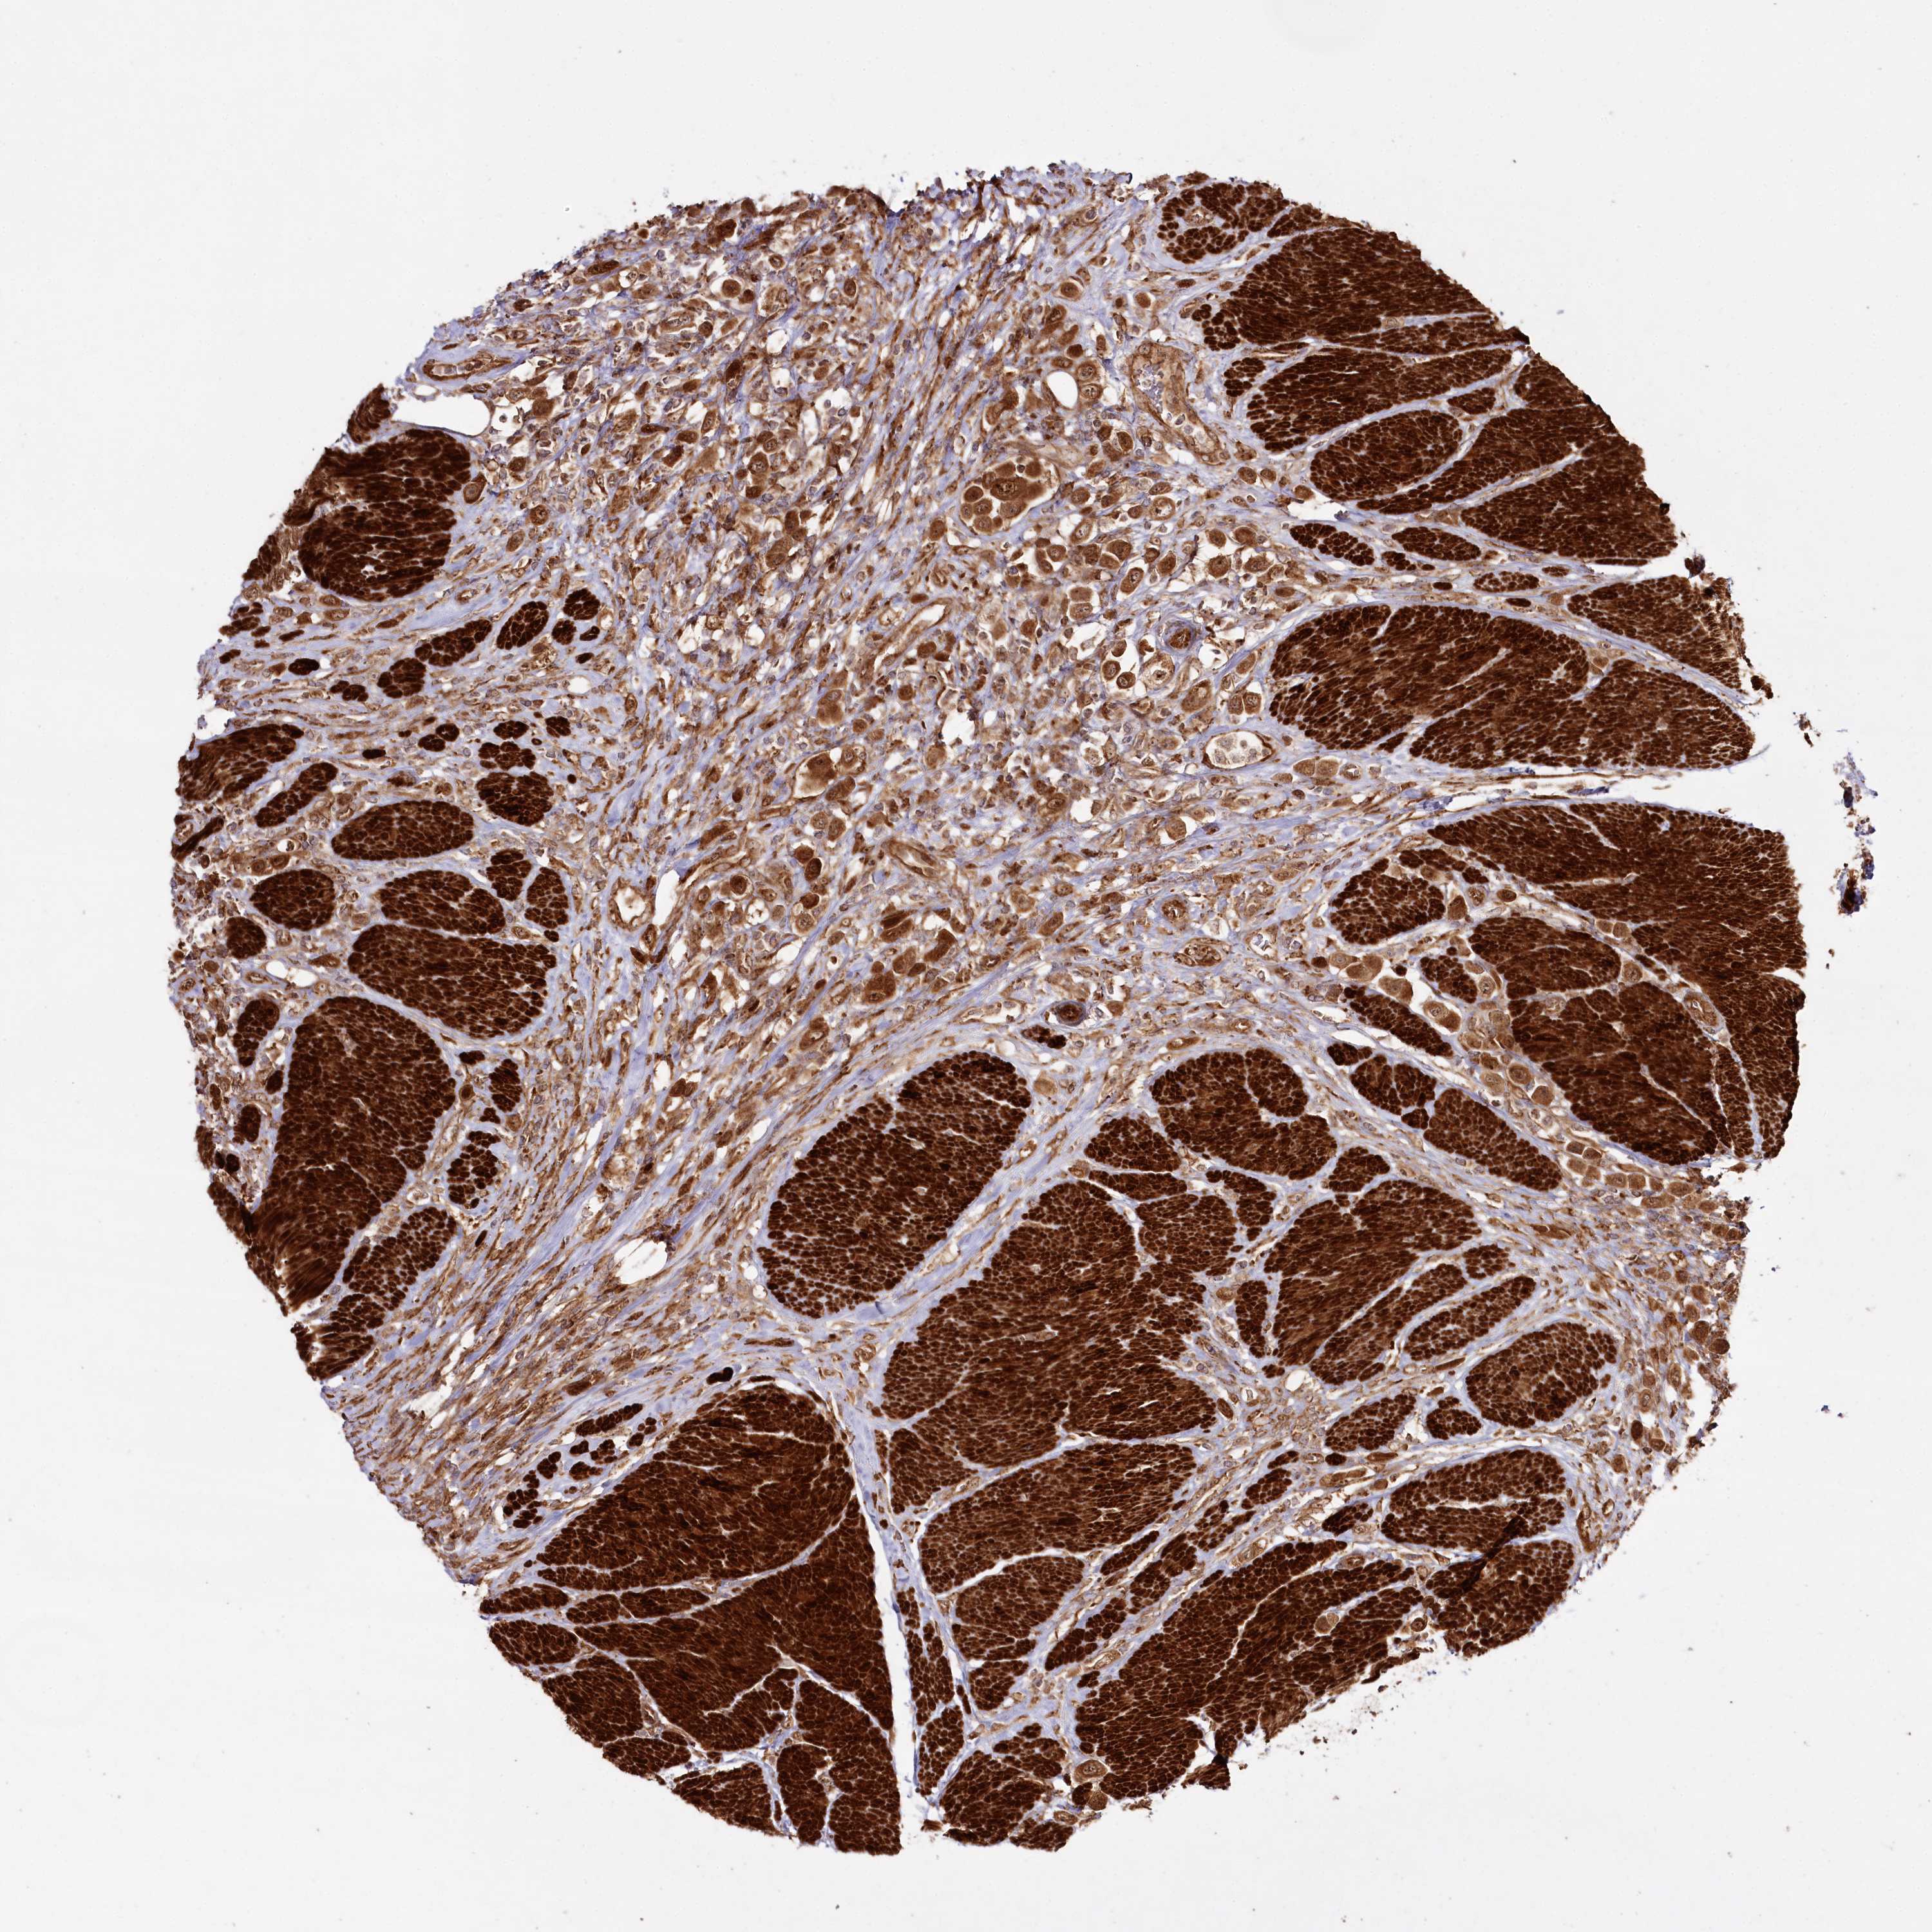

UROTHELIAL CANCER - Protein expressioni

A mouse-over function shows sample information and annotation data. Click on an image to view it in a full screen mode. Samples can be filtered based on level of antibody staining by selecting one or several of the following categories: high, medium, low and not detected. The assay and annotation is described here.

Antibody stainingi

Antibody staining in the annotated cell types in the current human tissue is reported as not detected, low, medium, or high, based on conventional immunohistochemistry profiling in selected tissues. This score is based on the combination of the staining intensity and fraction of stained cells.

Each image is clickable and will lead to virtual microscopy that enables deeper exploration of all samples and also displays staining intensity scores, fraction scores and subcellular localization as well as patient and tissue information for each sample.

Antibody HPA038450

Antibody HPA038451

Staining

High

Medium

Low

Not detected

Intensity

Strong

Moderate

Weak

Negative

Quantity

>75%

75%-25%

<25%

None

Location

Nuclear

Cytoplasmic/membranous

Cytoplasmic/membranous,nuclear

Urothelial carcinoma, High grade

Urothelial carcinoma, Low grade

Urothelial carcinoma, NOS